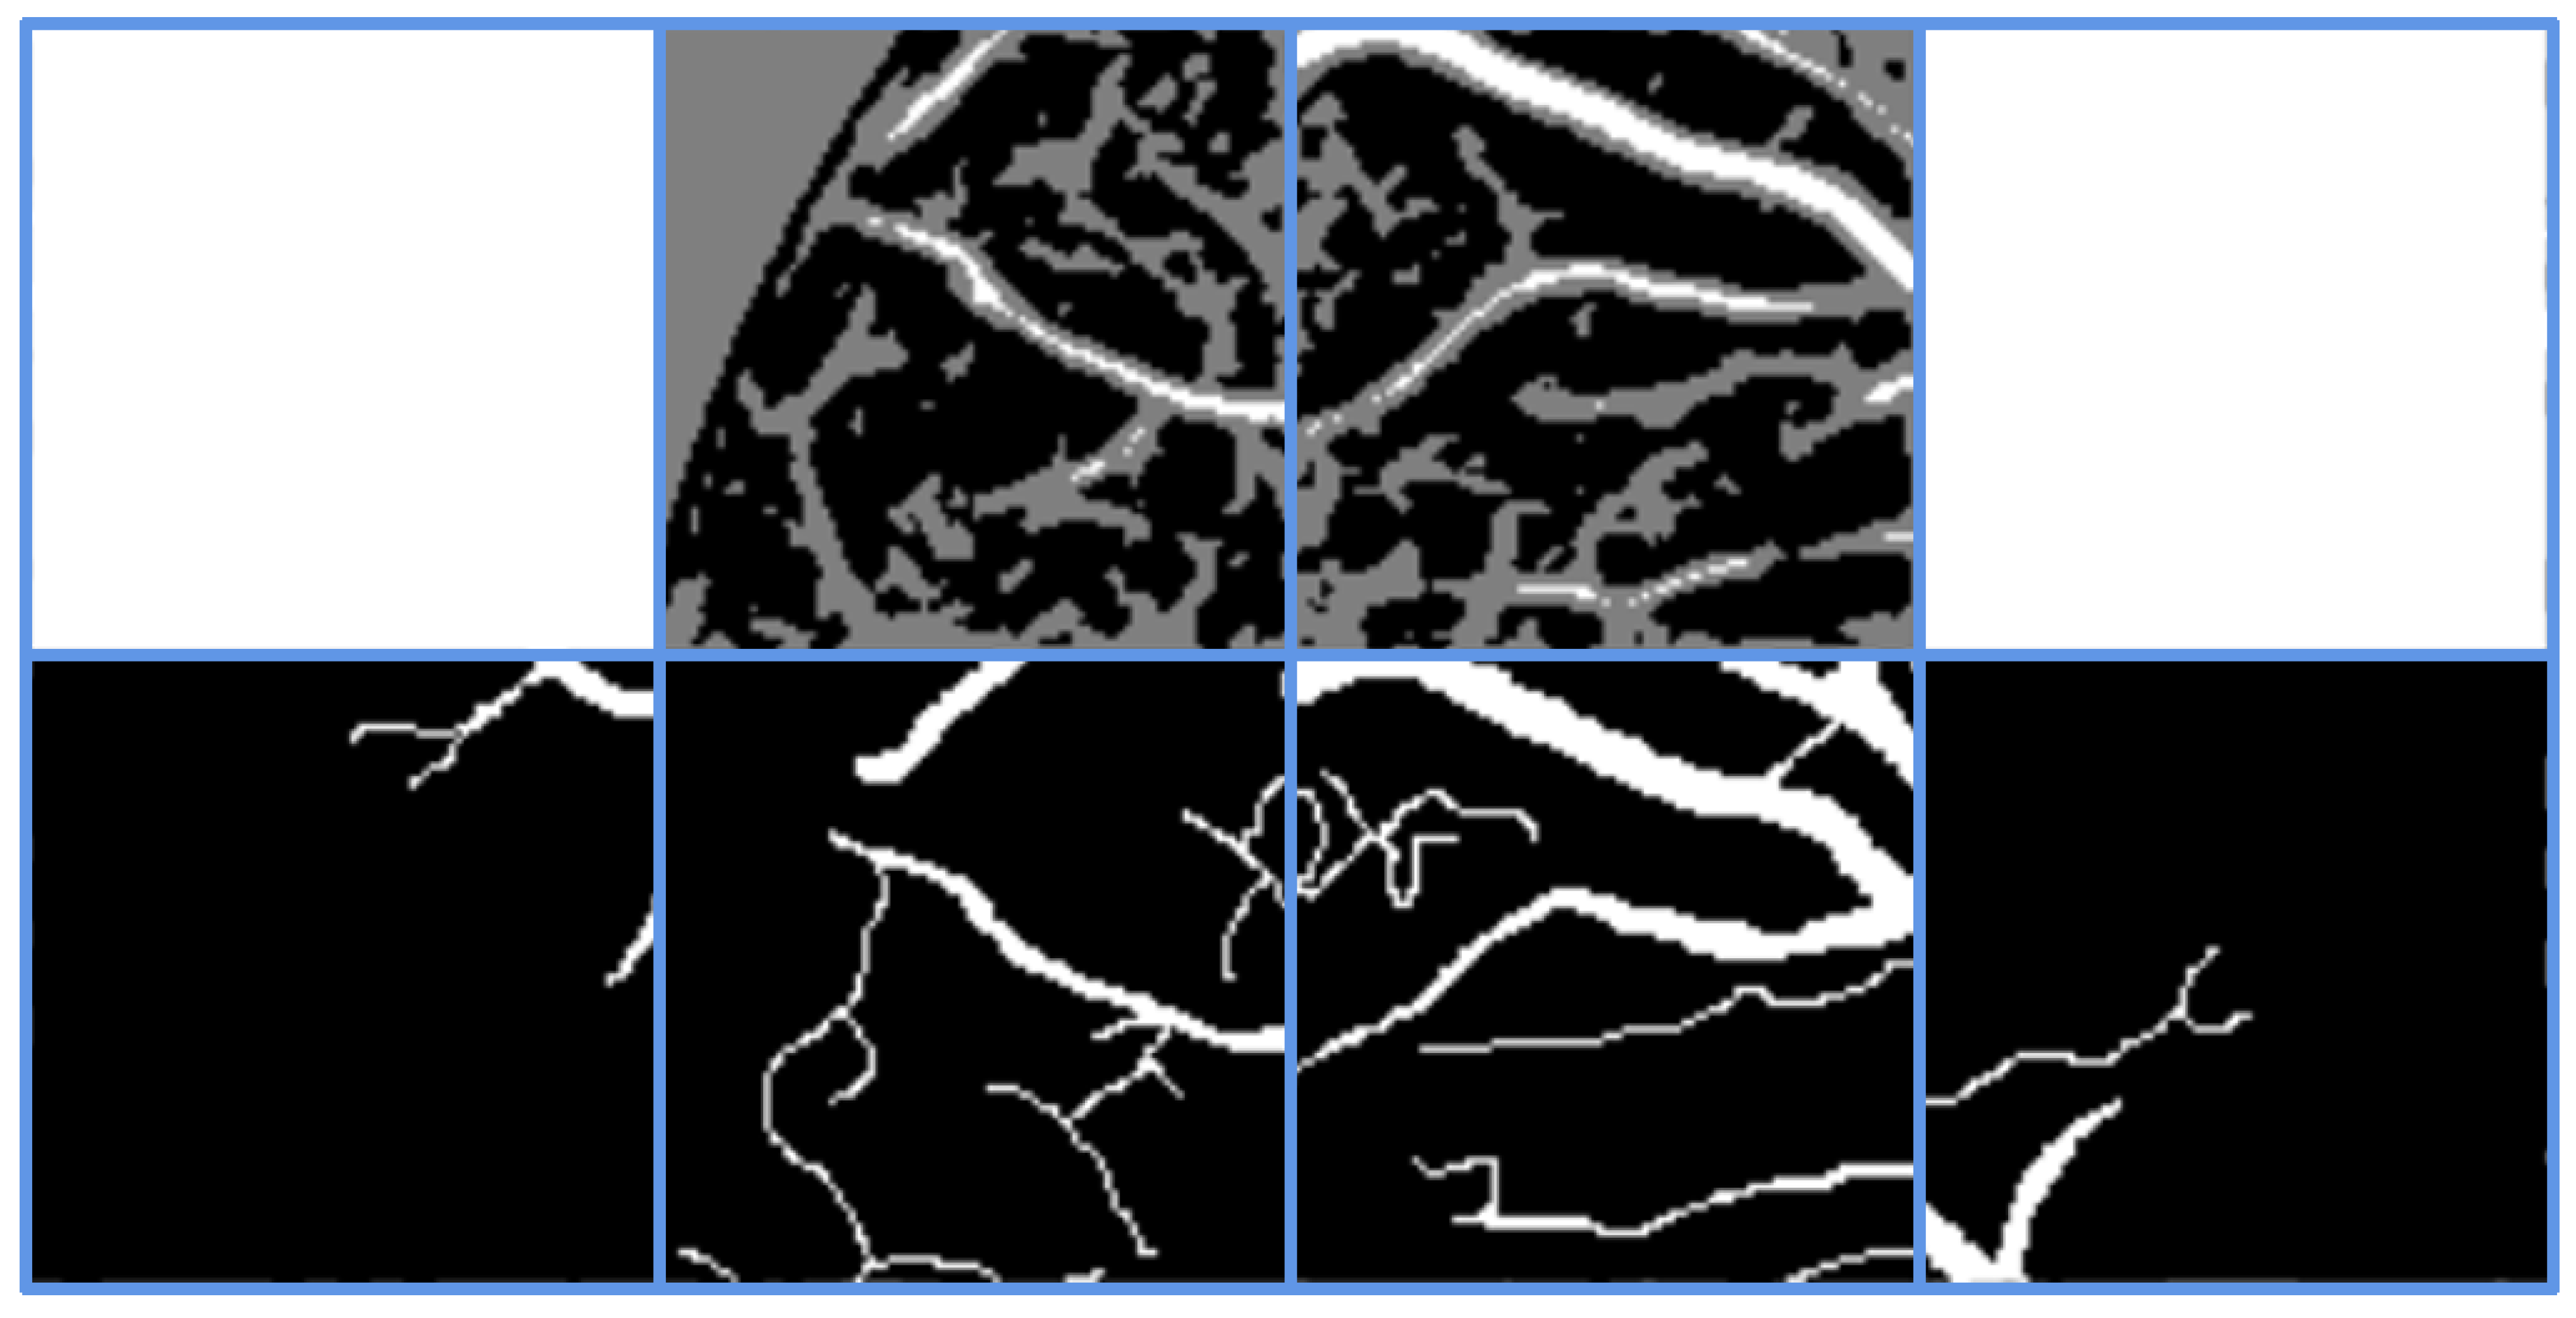

Figure 4 displays the retained (white regions, i.e., S m = 1 ) and discarded (black regions, i.e., S m = 0 ) pixels obtained through the three filtering strategies across five iterations. The fourth row represents the combined retained or discarded pixels from the first three strategies. The final row shows the pseudo-labels obtained by integrating all three filtering processes, where white regions denote retained vessel pseudo-labels, black regions denote retained background pseudo-labels, and gray regions represent eliminated pseudo-labels during iterations.

Figure 4. Filtering strategy.

Symmetry 17 01462 g004